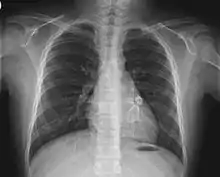

X-ray showing aneurysmal enlargement of the coronary arteries, which is a complication in a Kawasaki syndrome

Heart complications are the most important aspect of Kawasaki disease, which is the leading cause of heart disease acquired in childhood in the United States and Japan.[31] In developed nations, it appears to have replaced acute rheumatic fever as the most common cause of acquired heart disease in children.[15] Coronary artery aneurysms occur as a sequela of the vasculitis in 20–25% of untreated children.[52] It is first detected at a mean of 10 days of illness and the peak frequency of coronary artery dilation or aneurysms occurs within four weeks of onset.[48] Aneurysms are classified into small (internal diameter of vessel wall <5 mm), medium (diameter ranging from 5–8 mm), and giant (diameter > 8 mm).[31] Saccular and fusiform aneurysms usually develop between 18 and 25 days after the onset of illness.[15]